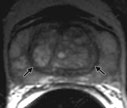

- Prostate magnetic resonance imaging (MRI) (www.radiologyresource.org/en/info.cfm?pg=mr_prostate): MRI provides views of the entire prostate with excellent soft tissue contrast.

Images: Images are shown for illustrative purposes. Do not attempt to draw conclusions or make diagnoses by comparing these images to other medical images, particularly your own. Only qualified physicians should interpret images; the radiologist is the physician expert trained in medical imaging.